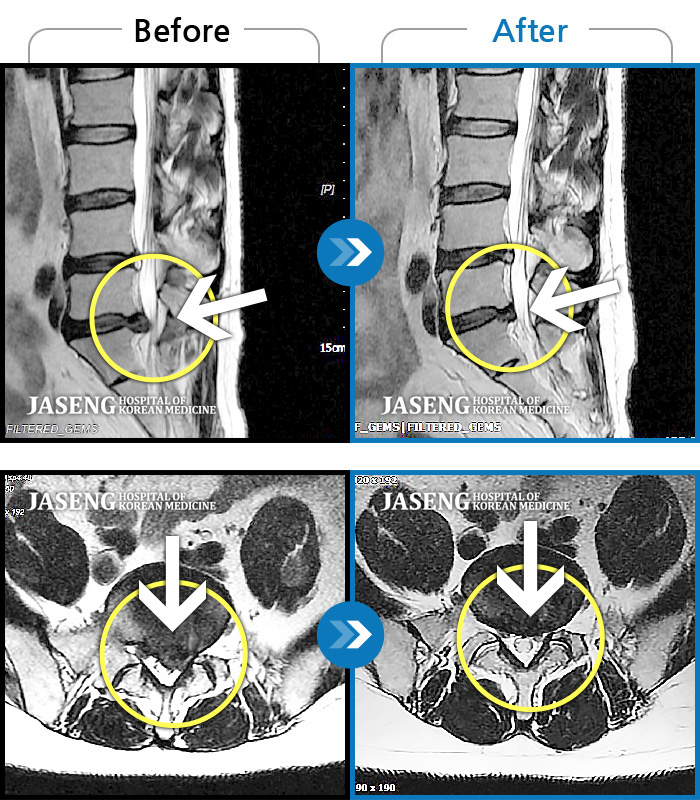

허리디스크

목동 · 고웅 원장

허리 통증과 우측 하지 방사통 극심한 상태

촬영시기

2010.07.30 ~ 2023.10.26

2023.12.08